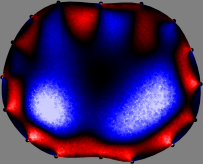

Refer to caption

Figure 2: Fidelity-embedded regularization method. (Left bottom) Correlations between four different column vectors (𝐒ksubscript𝐒𝑘{\bf S}_{k}) and all the remaining column vectors (𝐒subscript𝐒{\bf S}_{\ell}) are visualized. (Right bottom) Performances of the proposed fidelity-embedded regularization method for λ=𝜆\lambda=\infty are shown by numerical simulations.

To explain the FER method, we closely examine the correlations among column vectors of the sensitivity matrix 𝕊𝕊\mathbb{S}, described in Fig. 2. The correlation between 𝐒ksubscript𝐒𝑘{\bf S}_{k} and 𝐒subscript𝐒{\bf S}_{\ell} can be expressed as

for i=1,,16𝑖116i=1,\cdots,16[23]. This shows that the column vector 𝐒ksubscript𝐒𝑘{\bf S}_{k} is like an EEG (electroencephalography) data induced by dipole sources with directions uj,j=1,,16formulae-sequencesubscript𝑢𝑗𝑗116\nabla u_{j},j=1,\cdots,16 at locations ΔksubscriptΔ𝑘\Delta_{k}. Given that two dipole sources at distant locations produce mutually independent data, the correlation between 𝐒ksubscript𝐒𝑘\mathbf{S}_{k} and 𝐒subscript𝐒\mathbf{S}_{\ell} decreases with the distance between ΔksubscriptΔ𝑘\Delta_{k} and ΔsubscriptΔ\Delta_{\ell}. Fig. 2 shows a few images of the correlation 𝐒k,𝐒(|𝐒k||𝐒|)1subscript𝐒𝑘subscript𝐒superscriptsubscript𝐒𝑘subscript𝐒1\left\langle\mathbf{S}_{k},\mathbf{S}_{\ell}\right\rangle(|\mathbf{S}_{k}||\mathbf{S}_{\ell}|)^{-1} as a function of \ell for four different positions ΔksubscriptΔ𝑘\Delta_{k}. The correlation decreases rapidly as the distance increases. In the green regions where the correlation is almost zero, 𝐒subscript𝐒{\bf S}_{\ell} is nearly orthogonal to 𝐒ksubscript𝐒𝑘{\bf S}_{k}.